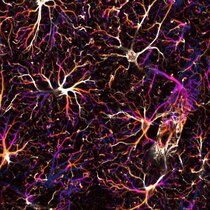

Astrozyten bilden im zentralen Nervensystem grosse Netzwerke miteinander verbundener Zellen. Werden diese Verbindungen im Gehirn erwachsener Mäuse…